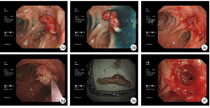

查体可见:腹部正中见陈旧手术瘢痕,切口中段见窦道形成,引流管在位,左下腹原手术部位见引流管在位,引流液均为脓性,左下腹触诊稍硬,轻压痛,无明显反跳痛(图1)。

结肠镜(2020年9月10日)提示:距肛缘约15cm可见结肠吻合口,通肠;吻合口左前壁可见肉芽增生及数枚吻合钉。经腹壁窦道注射美兰溶液,可见蓝色液体经此流出,证实为瘘口,随即去除吻合钉及肉芽增生,清理窦道时可见纱布样异物经瘘口至肠腔,用圈套器套扎后予以取出,证实为纱布(图3)。

入院后,予以禁食、抑酸及肠外营养支持等治疗,完善相关检查及化验,经窦道造影及腹部CT明确诊断为乙状结肠吻合口瘘。经肠镜证实患者存在窦道内异物,异物取出后继续予患者禁食、抑酸、肠外营养支持及双套管引流冲洗等治疗后患者脓腔较前明显减少(图4),于2020年9月24日再次行结肠镜检查,并在内镜下行OTSC夹闭术。此次结肠镜提示:距肛缘约15cm可见结肠吻合口,通肠;吻合口左前壁可见肉芽增生及数枚吻合钉。